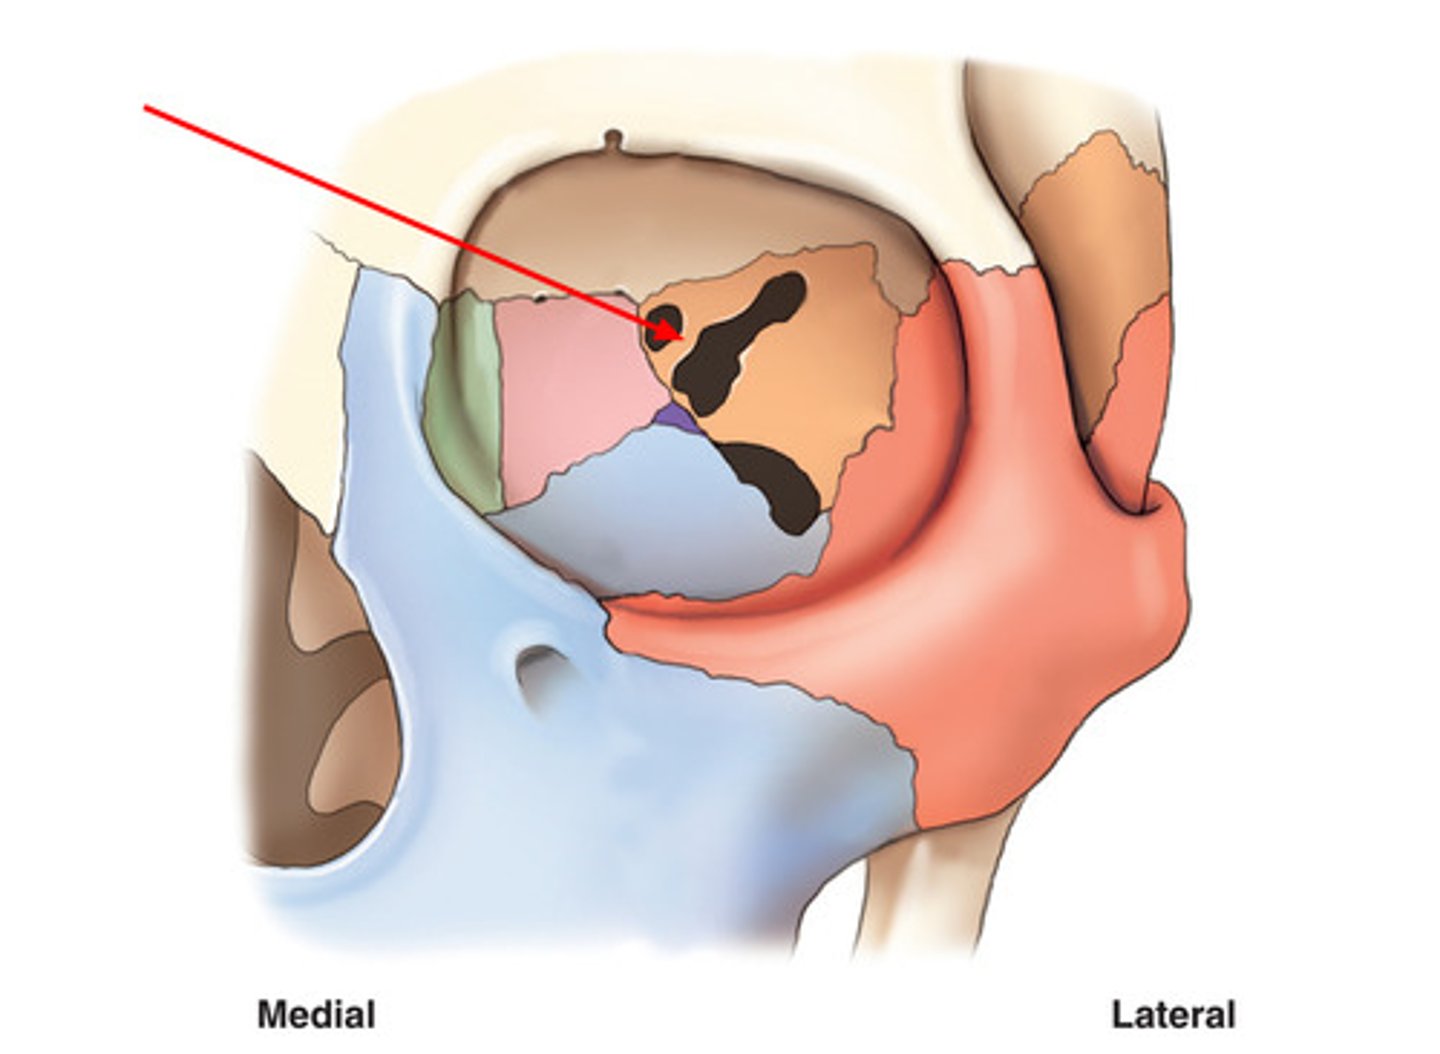

optic foramen in orbit

sphenoid strut